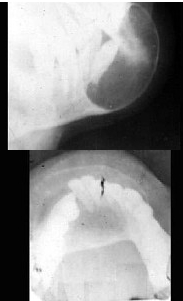

201、单项选择题

女,2岁,肘部外伤,如图所示,最佳的诊断为()

A.肱骨髁上骨折

B.肱骨髁上骨折并肘关节脱位

C.内上髁骨骺损伤

D.内上髁骨骺损伤并肘关节脱位

E.全骺分离

235、单项选择题

女,6岁,外伤后左肘部肿痛,活动受限,外髁局部压痛,X线摄片如图,最可能的诊断是()

A.左肱骨小头骨骺损伤

B.左肱骨髁上骨折

C.左肱骨外上髁骨骺损伤

D.左肱骨内髁骨骺损伤

E.左肱骨外髁骨骺损伤